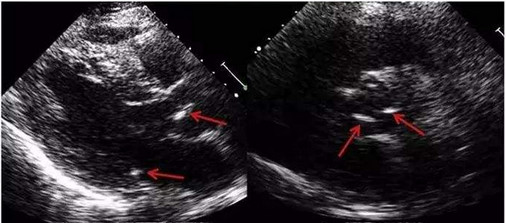

结果看什么?看那些威胁健康的“白色阴影”(图中标示箭头部位均为钙化部位)

超声心动图:心脏瓣膜钙化会在超声心动图中出现为强回声,也就是图中所示的白色部分。